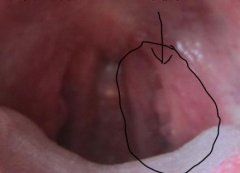

人类乳突病毒是一种分子较小(直径55nm)的DNA病毒,生物学上属Papovavirus科。已知的人类乳突病毒有一百多种基因型,其中有三十余种会感染人类生殖器官的皮肤及黏膜,造成各种疾病。尖锐湿疣不及时治疗的话对男性朋友的健康会产生一系列的危害。很多人因对尖锐湿疣的症状不了解而延误了疾病的最佳治疗时期。